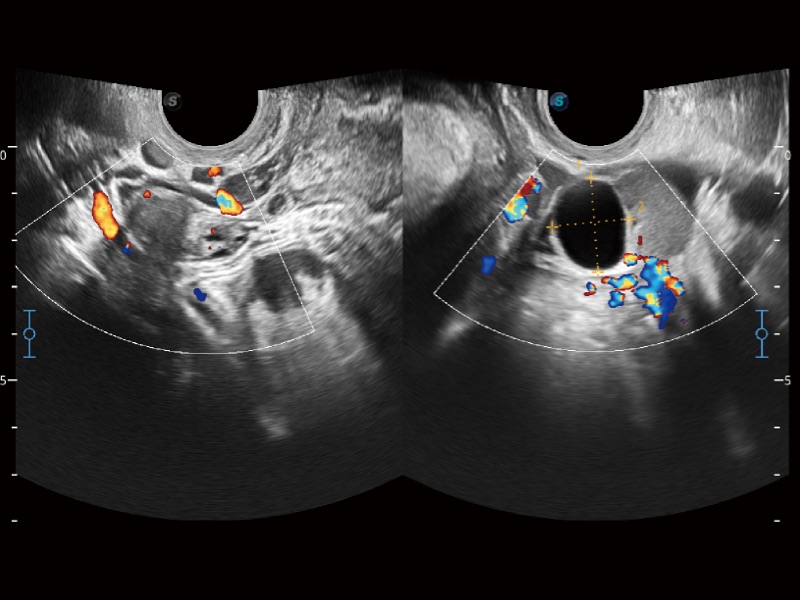

高分辨率血流成像技术提高了对低速血流信号的检测能力。在提高空间分辨率的同时,也克服了血流外溢现象,为用户提供更加真实的血流动力学信息。